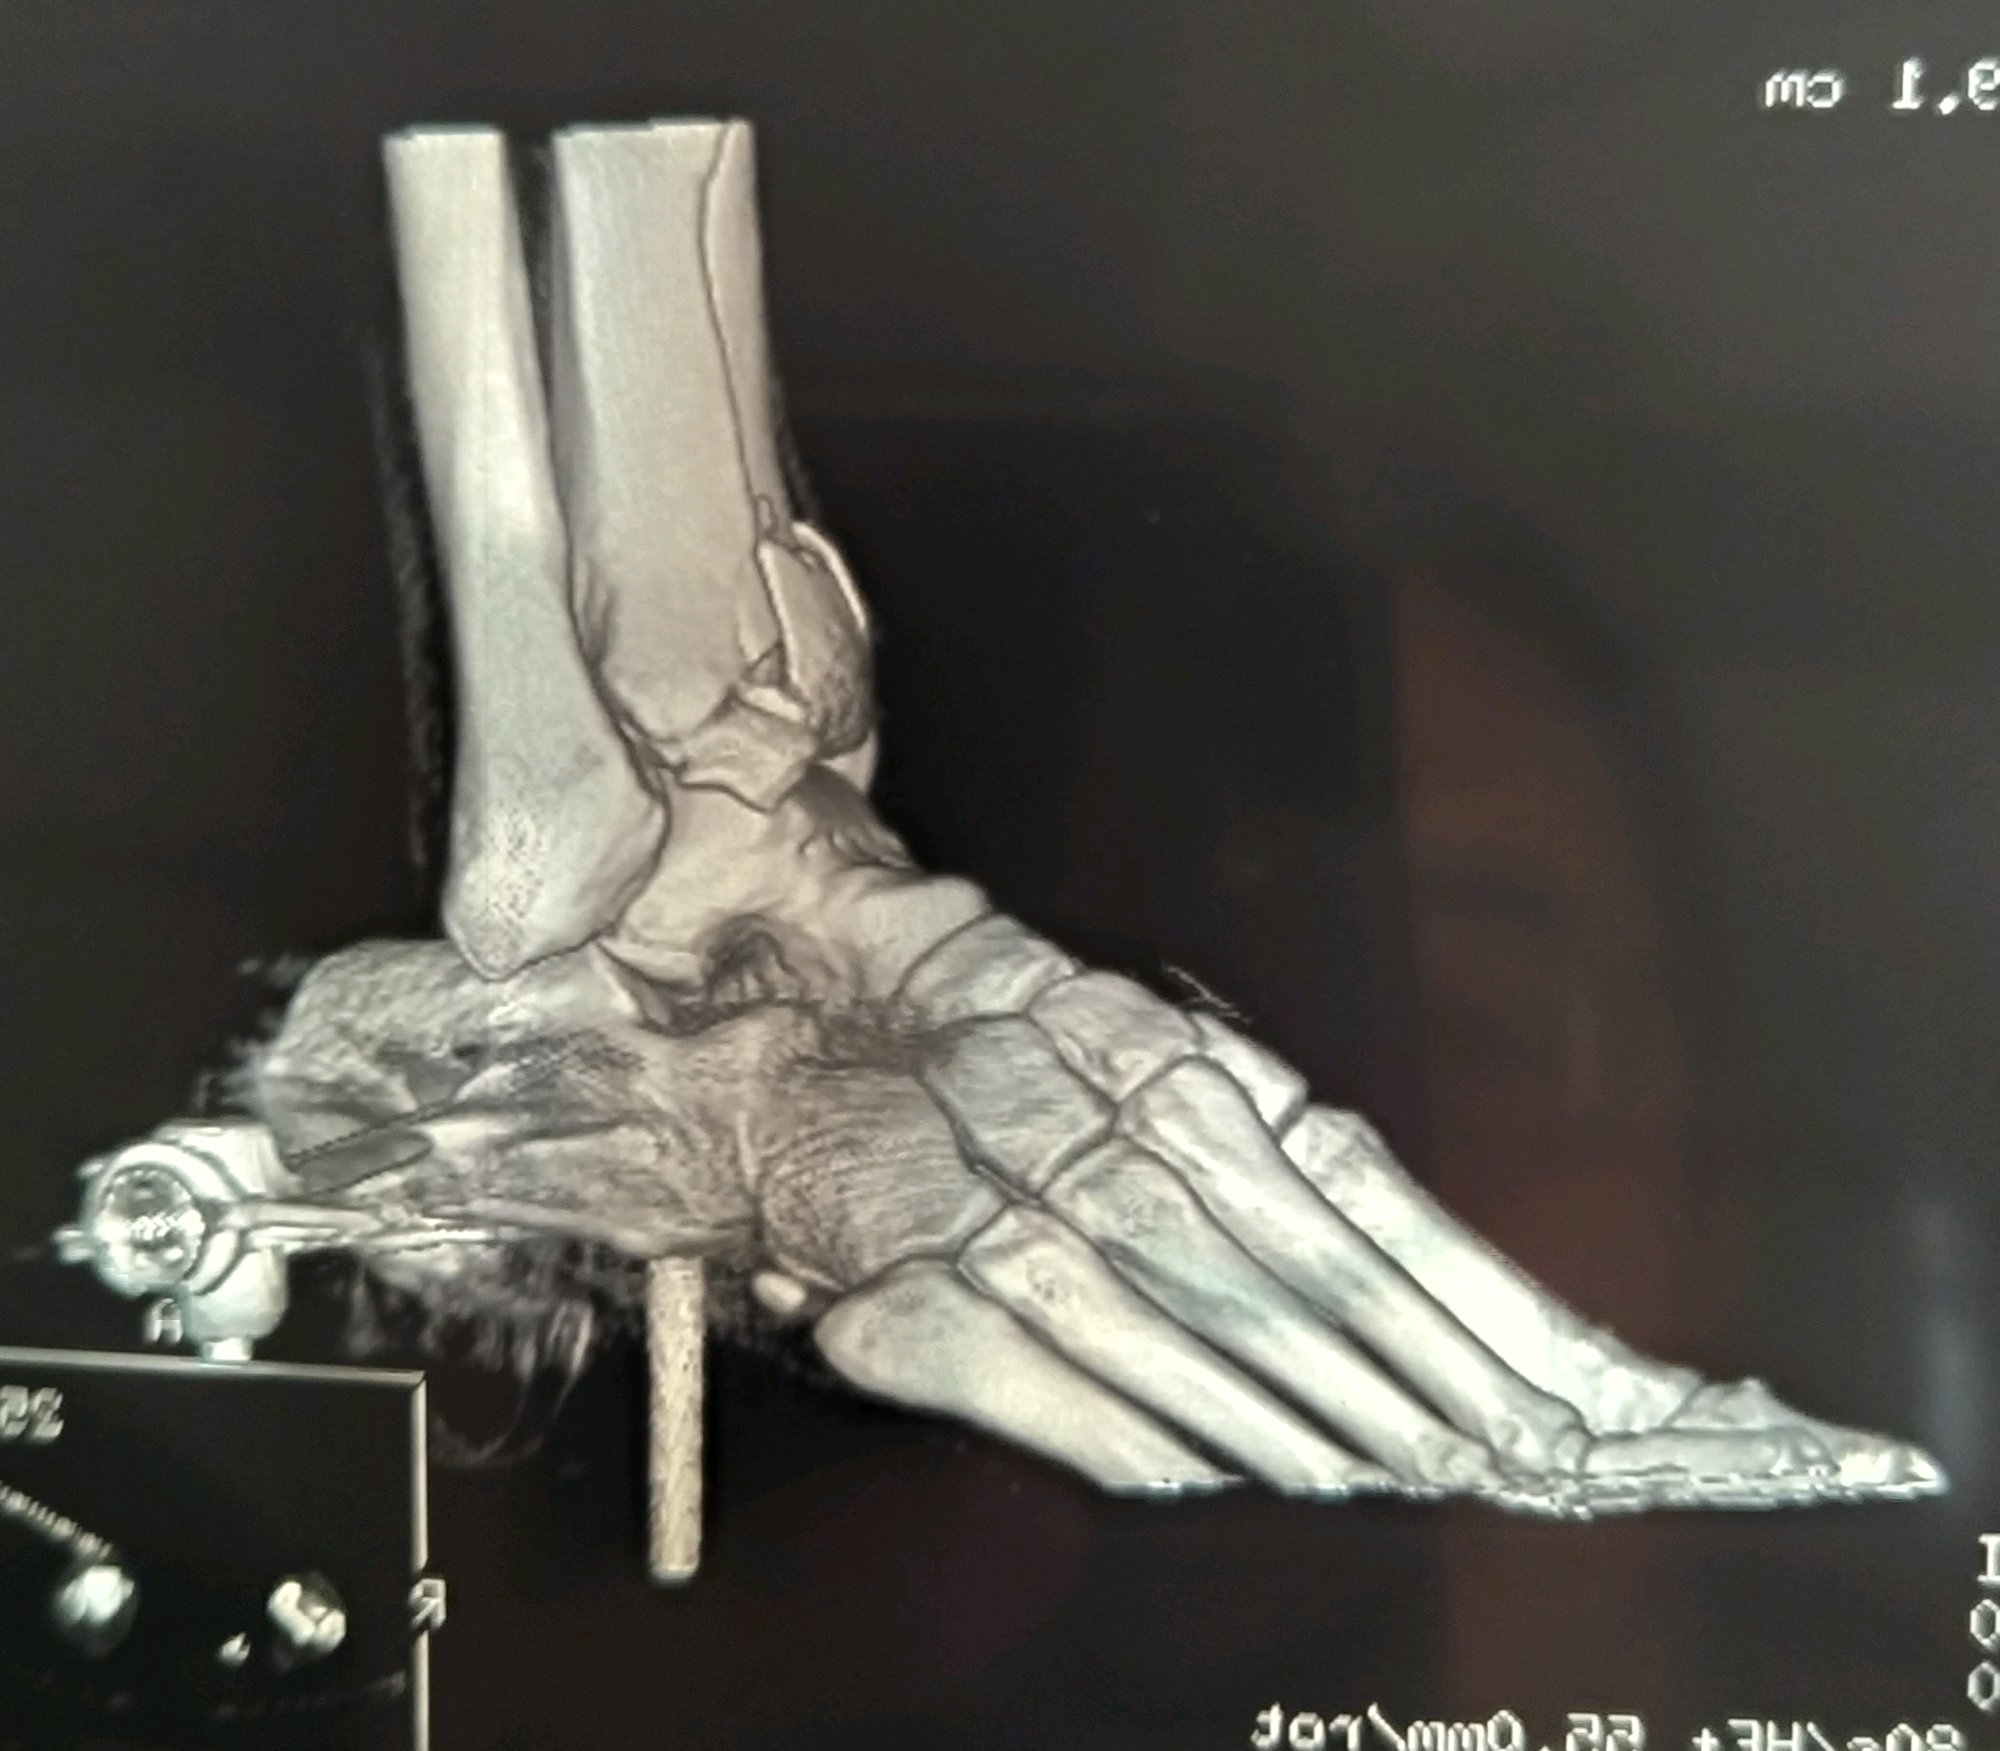

江苏扬州,男,43岁,月薪1w,工伤认定已完成。请问估计能定几级伤残,大概能赔偿多少?